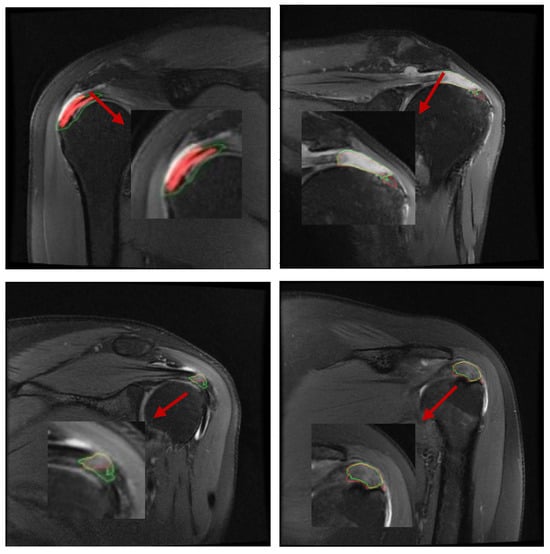

2.5. Automatic Segmentation of Predictions

Because the output of the deep neural network is two-channel, i.e., the output pixel points are predictively classified and assigned color values, it is possible to distinguish torn regions from normal regions by the difference in color values of the adjacent points [13]. Through continuous feedback learning, the deep learning network will give classification results for both color values, which can be evident within the software to see the segmented regions and boundaries (Figure 4), and thus be compared with the labels to calculate the relevant segmentation metrics [14]. In summary, the overall process of the segmentation algorithm is to first determine the approximate location of the torn region in the full image by the localization detection algorithm, and then to segment the torn region by classifying the pixel points into two categories, torn and normal, by operations such as convolution sampling classification.

Figure 4. Comparison between the physician-generated labels and the AI algorithm’s predicted segmentation results. The red regions represent manual segmentations by doctors, while the green contour outlines the AI’s predicted segmentation.